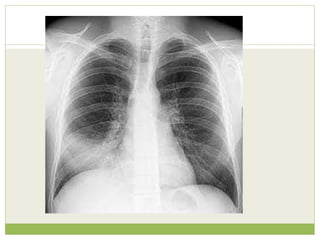

OPACIFICATION OF A

HEMITHORAX

๏‚— Pleural effusion

๏‚— Consolidation

๏‚— Collapse

๏‚— Massive tumour

๏‚— Fibrothorax

๏‚— Combination of above lesions

Pneumonectomy

๏‚— Lung agenesis